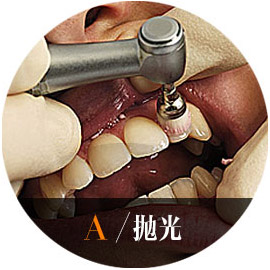

适应症:黄牙、黑牙、色素牙——冷光牙齿美白是将高强度冷光定点照射,可以去除牙齿表面的色素沉积,及深层所附着的色素,让您拥有一口润白亮泽的牙齿。具有持久、自然、快速、专业、安全等五大优势。

- 1.口腔检查 术前比色

- 2.药物保护 保护牙龈

- 3.冷光照射 迅速分解色素

- 4.术后保护 稳固美白效果